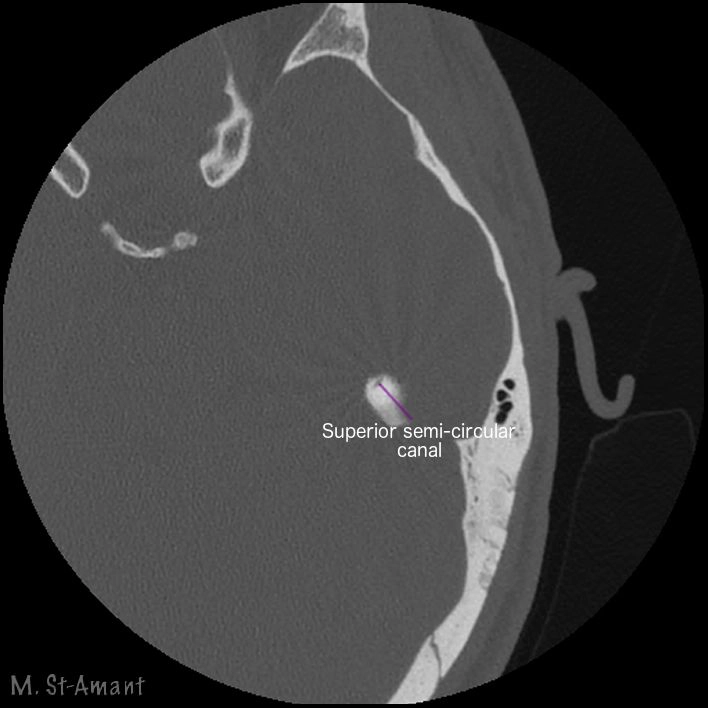

CT Xương thái dương